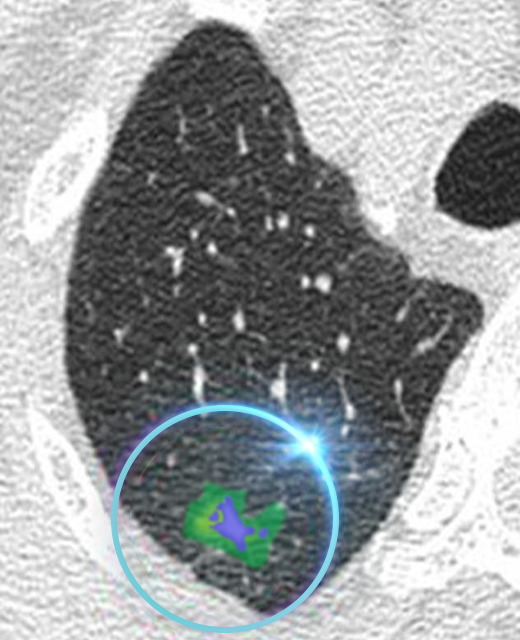

Ultra Low-Dose Scan

A regular scan at ultra-low dose radiation is noisy and unclear, making it possible to overlook a problem.

AIML

High-Dose Scan

The same scan with a higher dose of radiation reveals an abnormality.

AI Enhanced Ultra Low-Dose Scan

Our AI technology is able to sharpen the quality of the ultra-low dose scan to assist the doctor in early detection.

REiLi is our AI technology that uses deep learning and Fujifilm’s extensive image processing database to detect abnormalities automatically. This helps doctors accurately recognize the affected area and reduce the time taken by radiologists to interpret the scan.

FCT PixelShine is our Deep Learning based image processing software that improves the image quality of low-dose radiation scans. Sharper images have previously only been possible with high doses of radiation. FCT PixelShine enables our machines to produce a sharp, clear image even at ultra-low dose radiation.